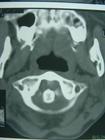

影像學檢查對確診及分型具有重要作用。

3.常規的X線平片及斷層攝影可獲得清晰的圖像;CT及MRI檢查不僅有助於顯示骨折線,且對寰椎橫韌帶的狀態便於觀察。應注意骨折移位程度,位移超過5mm者癒合多延遲。

此外,尚可依據頸咽間隙增寬(即咽後壁與第3頸椎椎體之間的距離,正常為4mm以內)進行判斷。根據X線平片、CT掃描及MRI等影像學檢查診斷上多無困難。